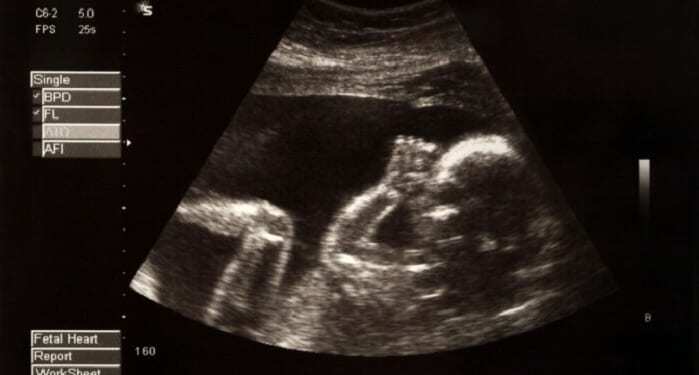

The law banned most abortions after approximately six weeks of pregnancy, when the unborn baby’s heartbeat can first be detected.